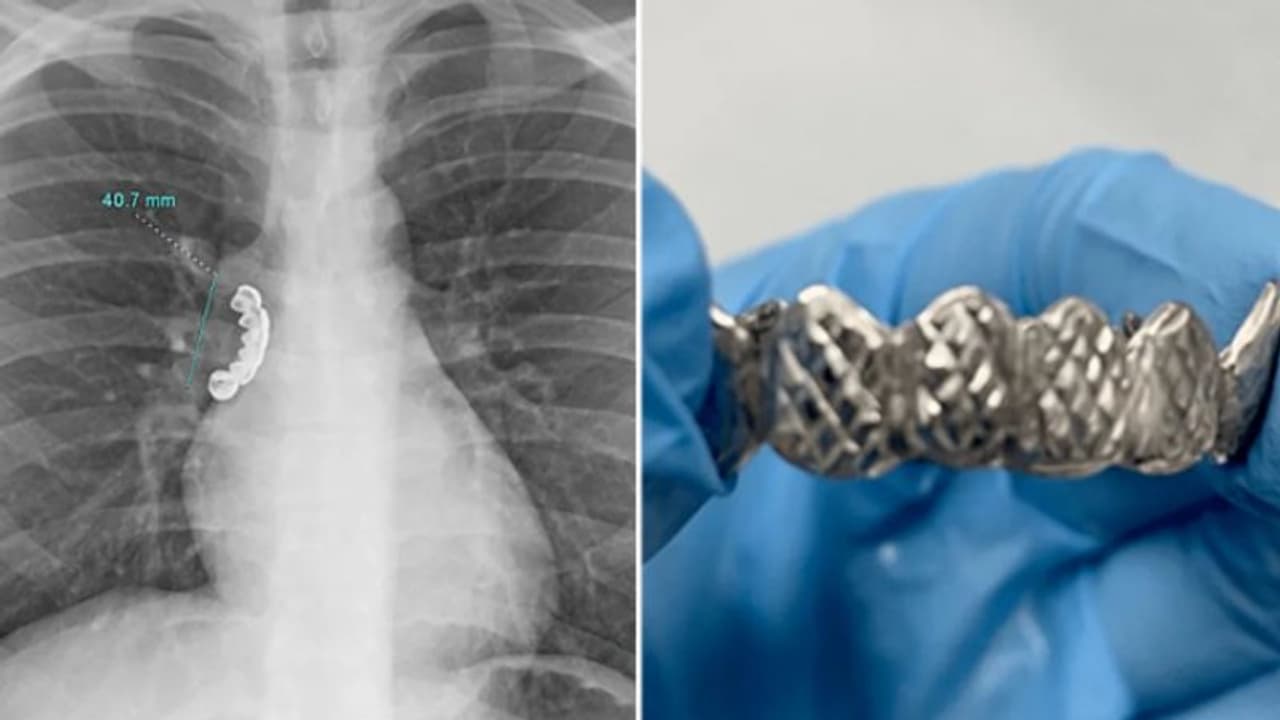

യുഎസിലെ വിസ്കോൺസിനിൽ 22 വയസുകാരന് അബദ്ധത്തിൽ വിഴുങ്ങിയത് സ്വന്തം വെപ്പു പല്ല്. വെള്ളിയില് പൂശിയ ഈ വെപ്പു പല്ലുകള് ഇയാളുടെ ശ്വാസകോശത്തിൽ കുടുങ്ങുകയായിരുന്നു. പെട്ടെന്ന് അപസ്മാരം ഉണ്ടായ സമയത്ത് ഈ വെപ്പ് പല്ല് ഇയാള് അറിയാതെ വിഴുങ്ങുകയായിരുന്നു എന്നാണ് ന്യൂയോര്ക്ക് പോസ്റ്റ് റിപ്പോര്ട്ട് ചെയ്യുന്നത്. അപകടത്തെത്തുടർന്ന് ഇയാള്ക്ക് അതിഭയങ്കരമായ ചുമയും ശ്വാസംമുട്ടലും അനുഭവപ്പെടുകയും ചെയ്തു.

മരണം വരെ സംഭവിക്കാന് സാധ്യത ഉണ്ടായിരുന്ന ഇയാളെ ഉടൻ തന്നെ ആശുപത്രിയിൽ എത്തിച്ചു. തുടര്ന്ന് ഇയാളുടെ എക്സ്-റേ പരിശോധിച്ചപ്പോഴാണ് ശ്വാസകോശത്തിന്റെ ശ്വാസനാളത്തിൽ 4.1 സെന്റീമീറ്റർ ദീളമുള്ള വെപ്പു പല്ല് കുടുങ്ങിയതായി ഡോക്ടര്മാര് കണ്ടെത്തിയത്. ക്യൂറസ് മെഡിക്കൽ ജേണലിൽ ആണ് ഈ സംഭവത്തിന്റെ കേസ് സ്റ്റഡി പ്രസിദ്ധീകരിച്ചത്.

പരിശോധനകൾക്ക് ശേഷം, കുടുങ്ങിയ വസ്തു നീക്കം ചെയ്യുന്നതിനായി ഡോക്ടർമാർ ഇയാളെ ബ്രോങ്കോസ്കോപ്പിക്ക് വിധേയമാക്കി. കനംകുറഞ്ഞ ട്യൂബ് ശ്വാസനാളത്തിലൂടെ പ്രവേശിപ്പിച്ചാണ് ഈ ശസ്ത്രക്രിയ ചെയ്തത്. ശസ്ത്രക്രിയ വിജയകരമായി നടന്നും എന്നും റിപ്പോര്ട്ടില് പറയുന്നു.